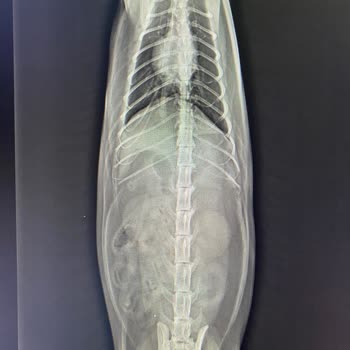

Nachdem ich dieses Futter meiner Katze gegeben hatte, wurde sie krank. Ich brachte sie zum Tierarzt, der eine Lebensmittelvergiftung diagnostizierte und sagte, dass sie vom Nassfutter stamme. Nach zwei Injektionen kehrten wir nach Hause zurück. Als es meiner Katze schlechter ging, brachte ich sie er...